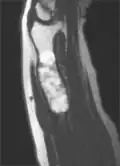

MRI showing enchondromas localized in the lower part of the radius of a 37-year-old patient affected with Ollier disease -

MRI showing enchondromas localized in the lower part of the radius of a 37-year-old patient affected with Ollier disease. -

Magnetic resonance imaging (MRI), ultrasound, and scintigraphy are generally not practical for diagnostic purposes. X-rays are not as effective in the monitoring or evaluation of enchondromas due to frequent localized changes also sometimes due to the large number of enchondromas. MRI can sometimes however be used to monitor and evaluate symptomatic lesions in the case of potential malignant transformations.